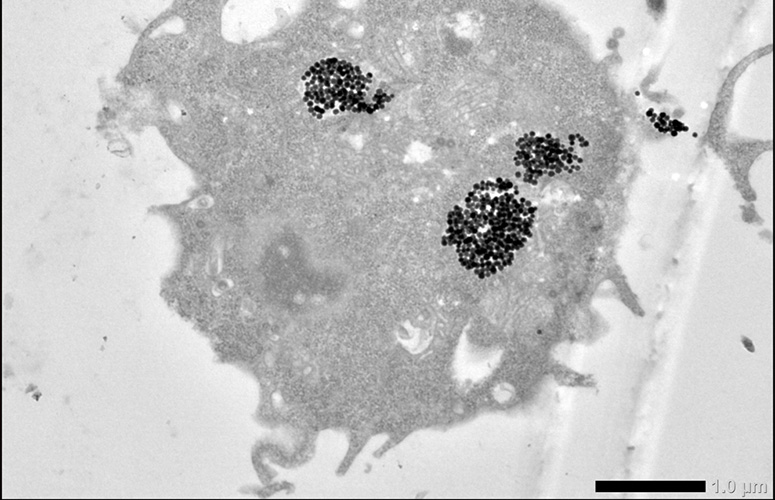

“Magnetosomek, sintesi kimikoko nanopartikula magnetikoek ez bezala, berezko mintz lipoproteiko bat dute, babestu egiten dituena eta, aldi berean, aglomeratzea saihesten duena. Gainera, funtzionalizatu egin daitezke, hau da, zenbait botika edo tumoreen aurkako eragile mintzean itsats daitezke, tumore-masaraino modu eraginkorrean gidatuak izan ahal izateko. Nanopartikula magnetikoek bero gisa igortzen dute kanpotik aplikatzen zaien eremu magnetiko alternoaren energia, eta, hala, tumoreen tenperatura igo eta aurre egiten diete”, adierazi du Muñozek.

“Magnetosomek beroa sortzeko gaitasun handia dute (sintesi kimikoko nanopartikula magnetikoak baino handiagoa), eta hipertermian duten eraginkortasuna baieztatu dute egindako esperimentuetan zelulen %80 hiltzen zirela ikustean”, esan du David Muñozek. Gainera, “hipertermia magnetikoak badu abantaila bat: terapia lokala da, eta ez du albo-ondorio larririk eragiten organismoan. Eremu magnetikoa ez da gorputzeko edozein tokitan aplikatu behar, ezta edozein modutan ere: tumoreak eragindako eremuan bakarrik aplikatu behar da, eta 43 eta 46 ºC arteko tenperatura lortu behar da, tenperatura-tarte horretan zelulak apoptosi deritzonean sartzen baitira —programatutako zelula-heriotza—. Frogatu dugu magnetosomak erabiliz hipertermia magnetikoak tenperatura igoera nahikoa ematen duela zelulen bideragarritasuna estatistikoki nabarmen murrizteko, eta zelulak apoptosian sartu eta hiltzera bultzatzen dituela”, azpimarratu du lanaren egileak.